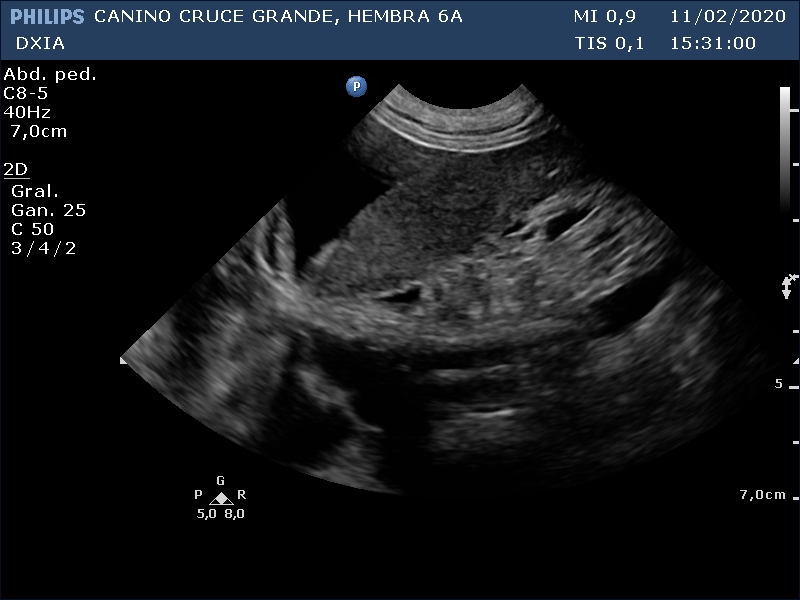

Se incluyen 3 imágenes del estudio:

Presencia de líquido libre abdominal. Bazo; no esplenomegalia, parénquima homogéneo. Se observa pequeño nódulo.